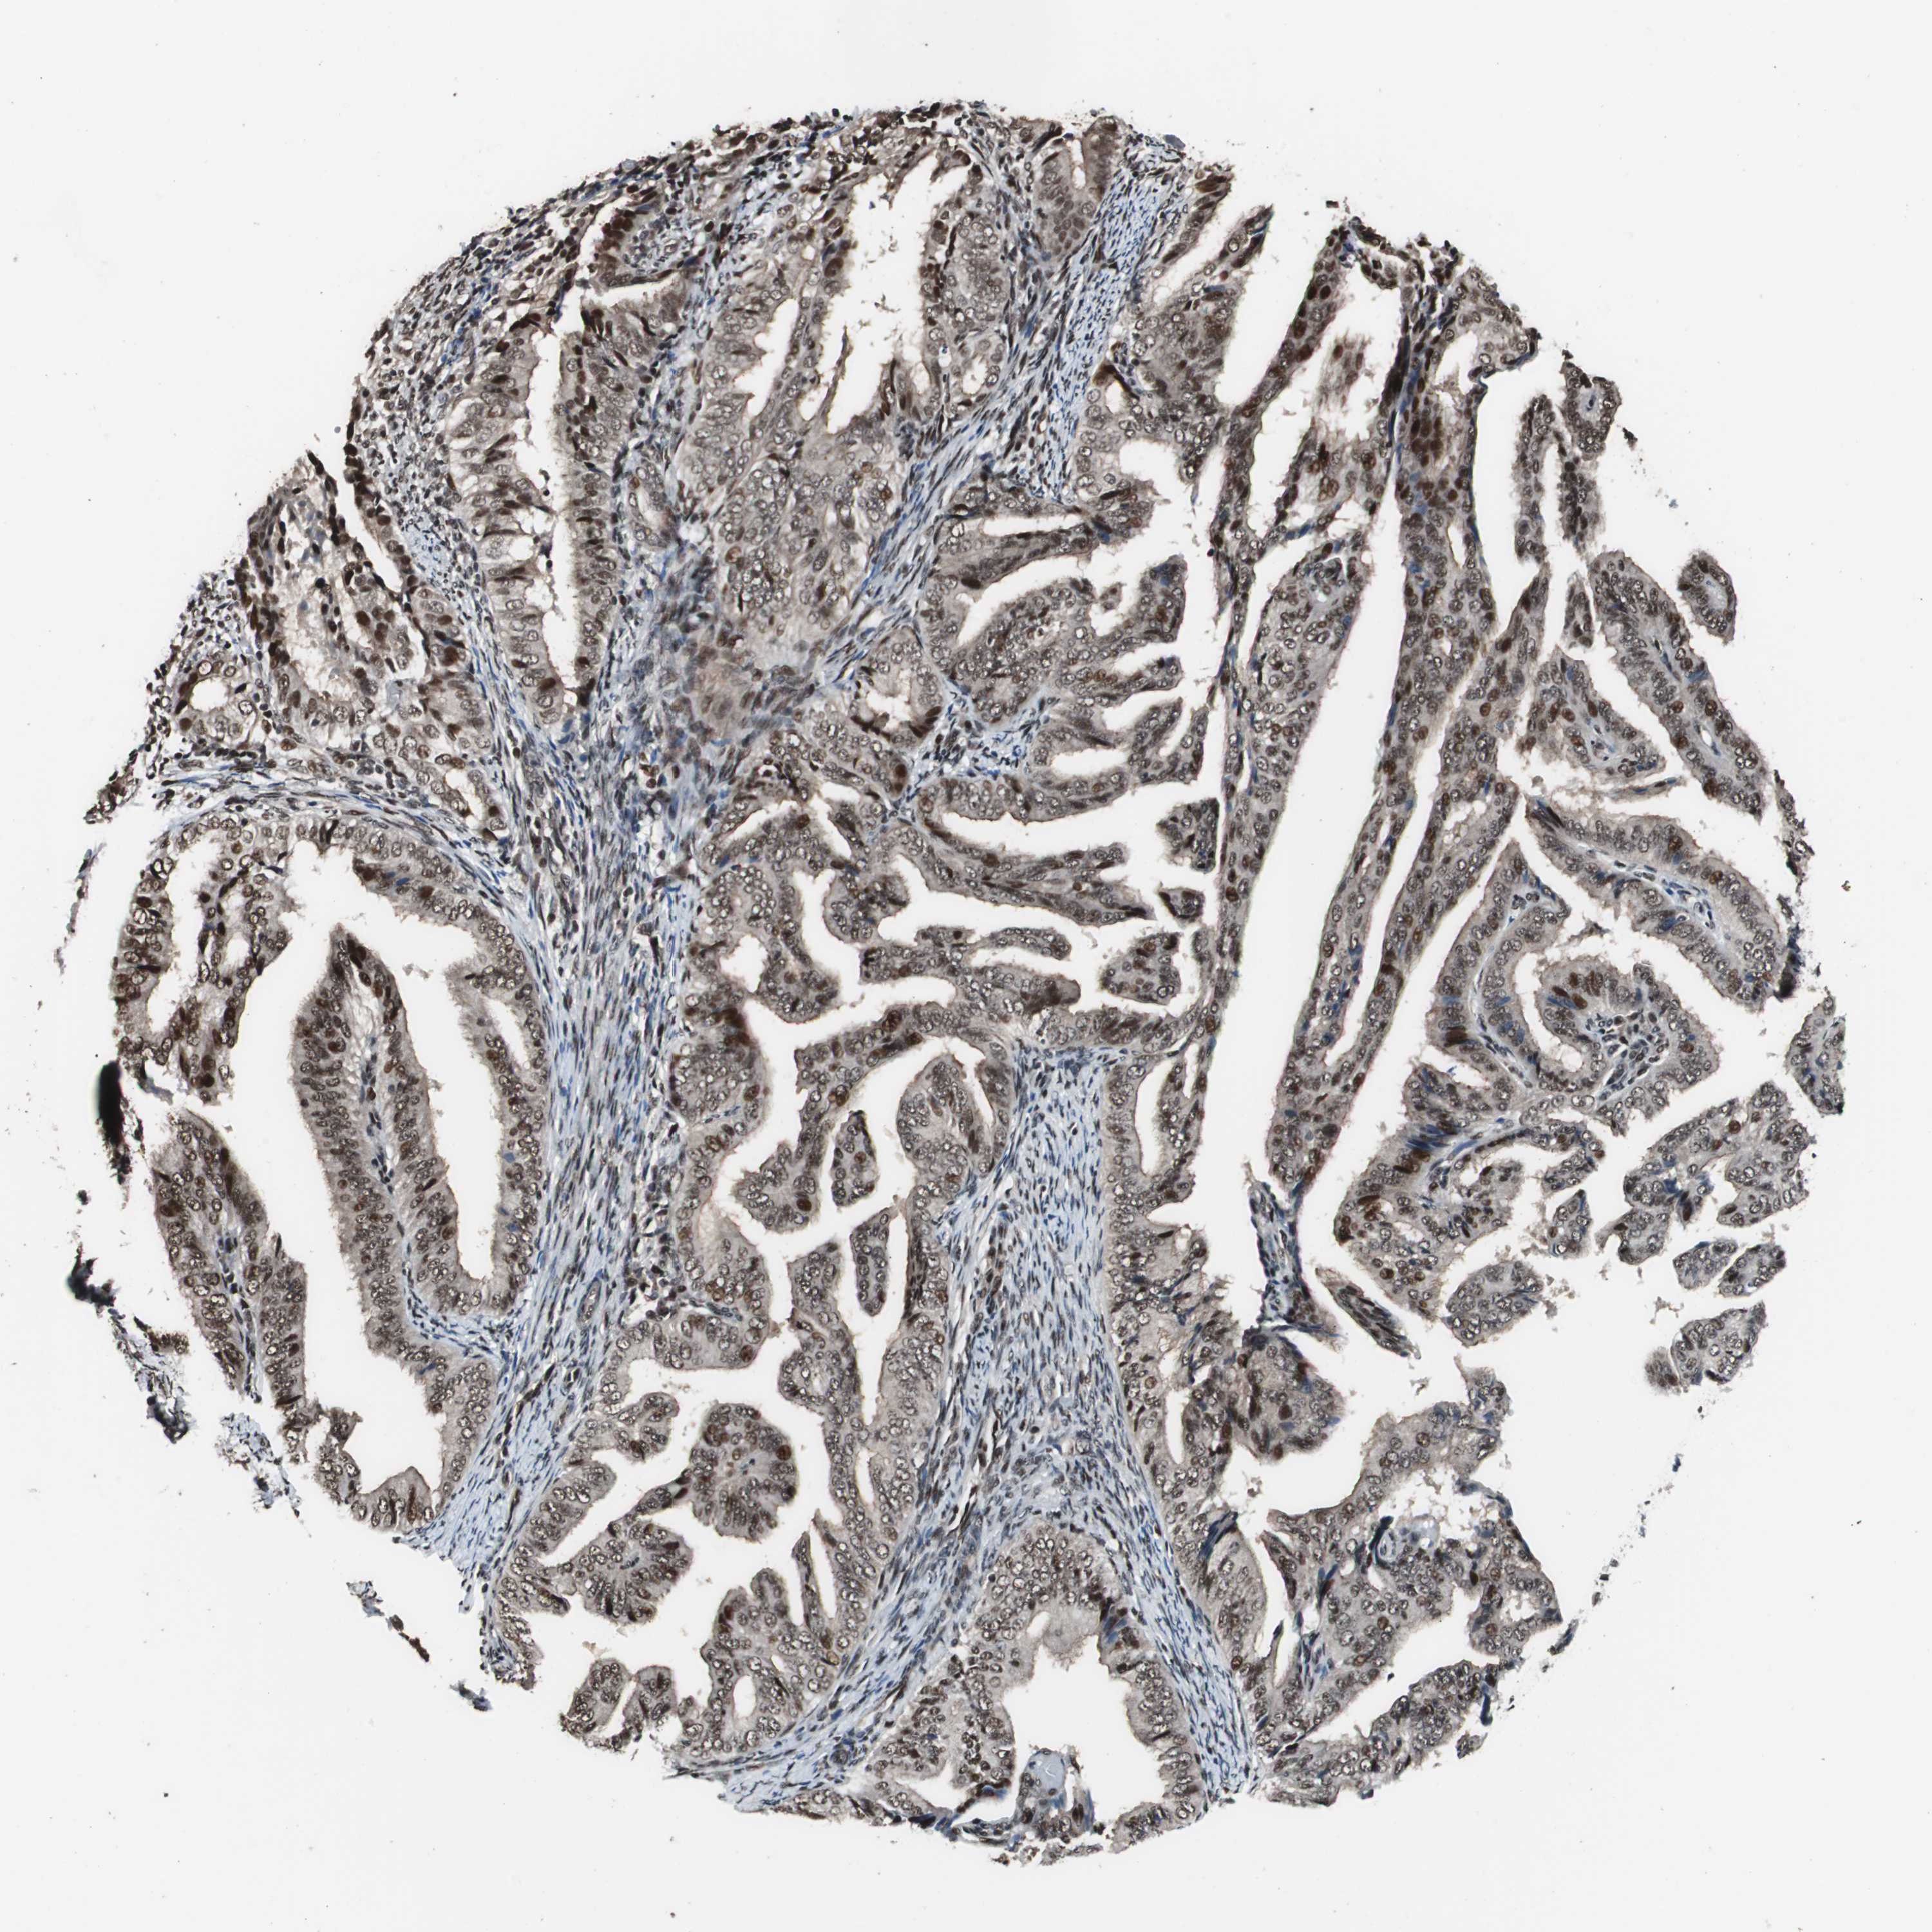

ENDOMETRIAL CANCER - Protein expressioni

A mouse-over function shows sample information and annotation data. Click on an image to view it in a full screen mode. Samples can be filtered based on level of antibody staining by selecting one or several of the following categories: high, medium, low and not detected. The assay and annotation is described here.

Note that samples used for immunohistochemistry by the Human Protein Atlas do not correspond to samples in the TCGA dataset.

Antibody stainingi

Antibody staining in the annotated cell types in the current human tissue is reported as not detected, low, medium, or high, based on conventional immunohistochemistry profiling in selected tissues. This score is based on the combination of the staining intensity and fraction of stained cells.

Each image is clickable and will lead to virtual microscopy that enables deeper exploration of all samples and also displays staining intensity scores, fraction scores and subcellular localization as well as patient and tissue information for each sample.

Antibody HPA006982

Staining

High

Medium

Low

Not detected

Intensity

Strong

Moderate

Weak

Negative

Quantity

>75%

75%-25%

<25%

None

Location

Nuclear

Cytoplasmic/membranous

Cytoplasmic/membranous,nuclear

Adenocarcinoma, NOS